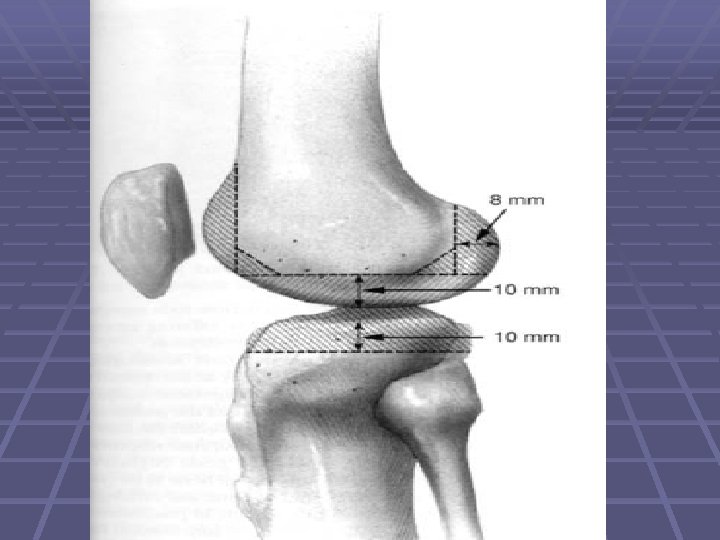

The Femoral Prep. § Augmentation of the femoral condyles distally or posteriorly or both is needed to balance the flexion and extension gaps without significant joint line elevation. § Use a larger femoral component in the anteroposterior dimension, with distal and posterior metal augmentation

The Femoral Prep. Cont. § Rotation of the femoral component should be determined using the epicondylar axis

The Femoral Prep. § Bone defects on the femur generally are managed with metal augmentation § Small defects and larger defects can be filled with cement